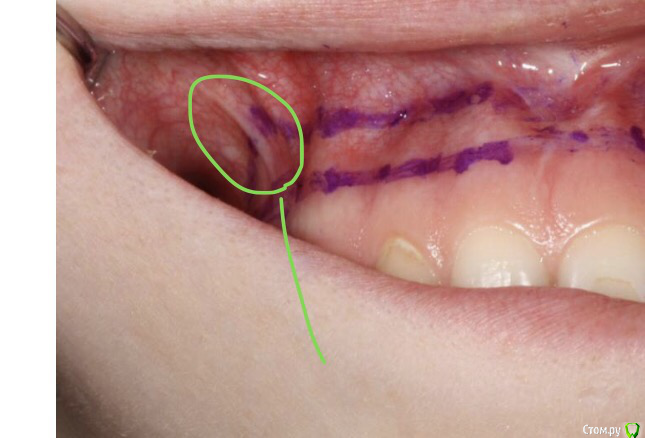

Romanson Опубликовано 12 февраля, 2019 Автор Поделиться Опубликовано 12 февраля, 2019 Вот эти тяжи тоже иссекаются? Ссылка на комментарий

EdGein Опубликовано 12 февраля, 2019 Поделиться Опубликовано 12 февраля, 2019 10-12 мм это в среднем.А так нужно замерять от зенита до края губы.Полоска иссекается до мышц. Травматичность минимальна, может быть небольшой отек, но не всегда.Уздечка и тяжы иссекаются, хотя есть методики в обход уздечки. 1 Ссылка на комментарий